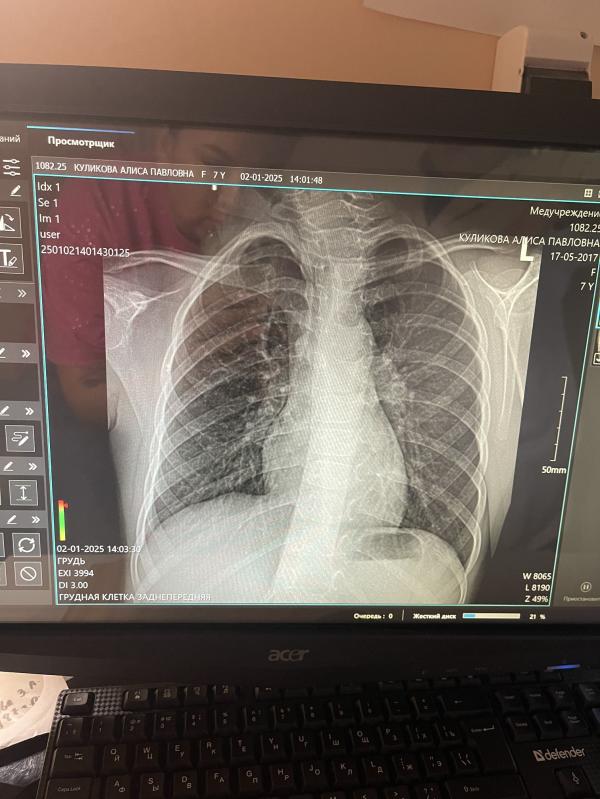

По рентгену поставили дочке бронхитическую картину легких.

Но мне написали,что очень положе на пневмонию.

Рентген видит пневмонию. А какая она определяется анализом крови.

Пневмонии по снимку нет